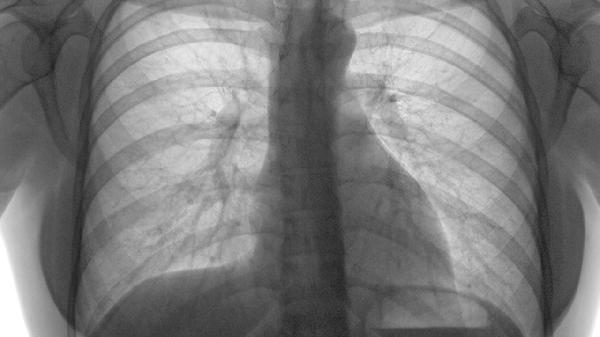

肺部结节可分为单发和多发两种类型,主要通过影像学检查判断数量差异,单发指孤立性结节,多发指同时存在两个及以上结节。

单发结节通常表现为肺组织内单个圆形或类圆形病灶,直径多在30毫米以内,边界可能清晰或模糊。这类结节常见于结核球、错构瘤或早期肺癌,需结合结节形态、生长速度及患者吸烟史综合评估。CT检查可显示钙化、毛刺征等特征,增强扫描有助于鉴别良恶性。对于8毫米以上的实性结节或6毫米以上的磨玻璃结节,建议3-6个月随访复查。

多发结节多呈现双肺散在分布,常见于感染性病变、转移性肿瘤或肉芽肿性疾病。转移瘤多位于肺外周,大小不等且边缘光滑;粟粒性结核则表现为均匀分布的1-2毫米小结节。需结合PET-CT或穿刺活检明确性质,若结节在短期内数量增加或体积增大,需警惕恶性肿瘤可能。对于免疫功能低下者出现的多发结节,应优先排查真菌或特殊病原体感染。